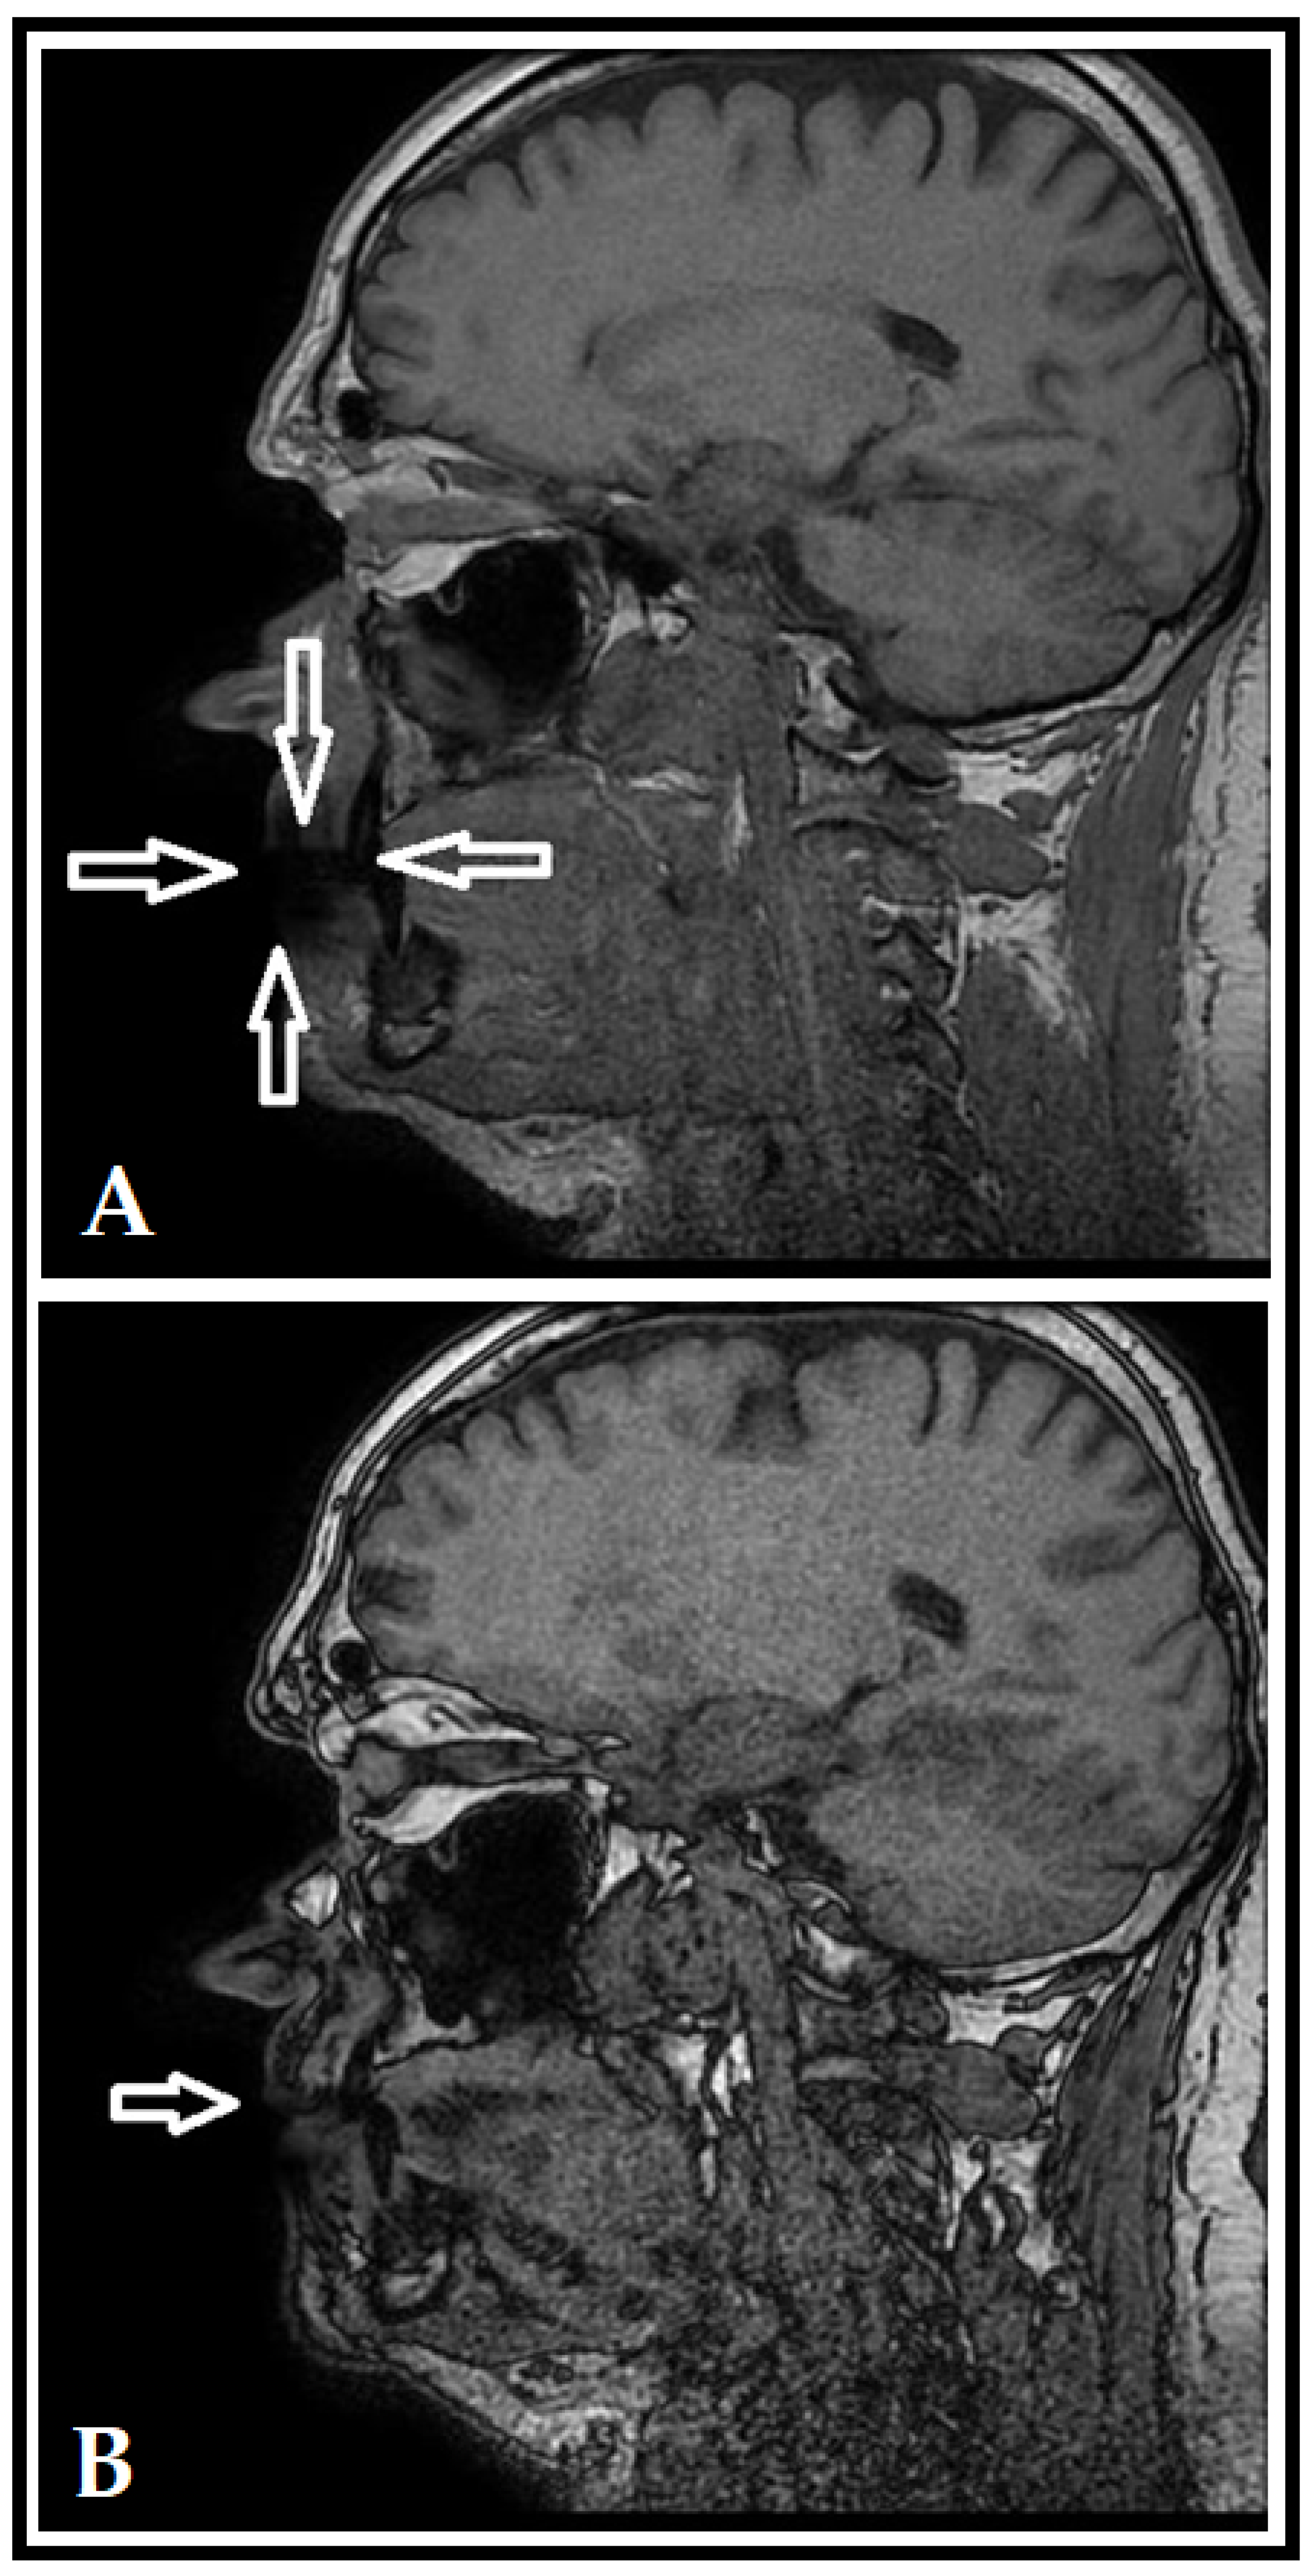

- Flügge, T.; Ludwig, U.; Amrein, P.; Kernen, F.; Vach, K.; Maier, J.; Nelson, K. MRI for the display of autologous onlay bone grafts during early healing—An experimental study. Dentomax. Radiol. 2020, 50, e2020068. [Google Scholar] [CrossRef]

- Wanner, L.; Ludwig, U.; Hövener, J.B.; Nelson, K.; Flügge, T. Magnetic resonance imaging—A diagnostic tool for postoperative evaluation of dental implants: A case report. Oral Surg. Oral Med. Oral Pathol. Oral Radiol. 2018, 125, e103–e107. [Google Scholar] [CrossRef] [PubMed]